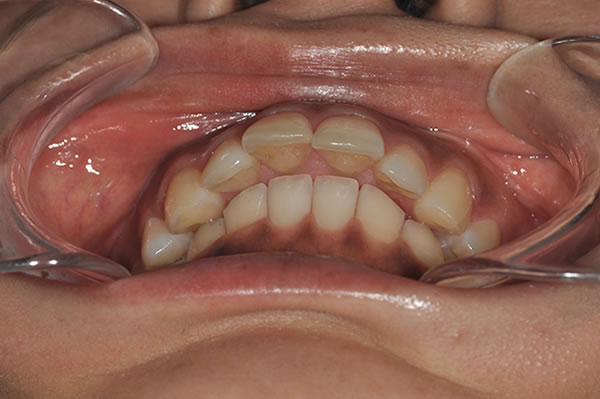

上顎前突症の治療例

上顎前突症(出っ歯)の矯正症例 ケース01

| 治療前(初診) | 治療後 | |